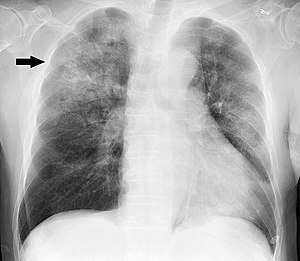

Diagnosis: how do you recognize pneumonia?

The doctor assesses the symptoms, asks about family history and examines the lungs.

He may do an x-ray of the lungs and request an analysis of pulmonary secretions (expelled by coughing). If needed, he will have to do other tests, such as looking for bacteria in the blood.